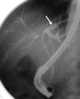

Chemotherapy-induced cystitis

Hemorrhagic cystitis or haemorrhagic cystitis is an inflammation of the bladder defined by lower urinary tract symptoms that include dysuria, hematuria, and hemorrhage. The disease can occur as a complication of cyclophosphamide, ifosfamide and radiation therapy. [Source: Wikipedia ]